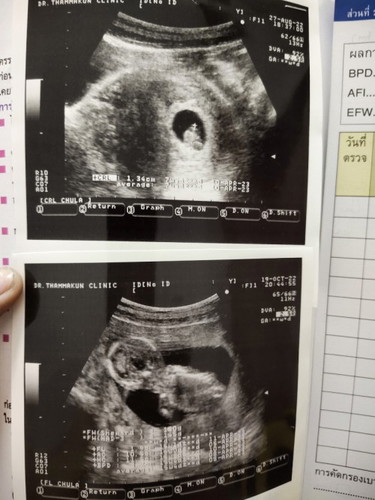

ขอดูเด็กอายุ 15 สัปดาห์

ขอดูเด็อายุ 15 สัปดาห์ของแม่ๆหน่อยค่ะ ได้ผู้ ญ หรือผู้ชายกันบ้าง 🥰🥰🥰

น้องเป็นผช. 15W4D ค่ะ